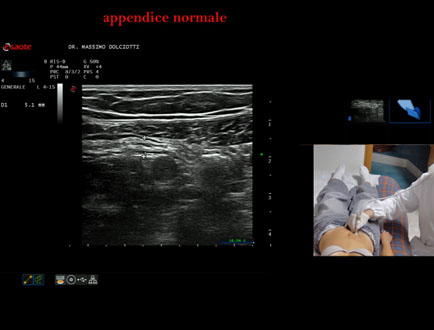

Età Paziente: F 24 anni

Motivazione dell'esame: da 3 mesi dolore al fianco destro.

Commento all'esame: le immagini ed il video documentano l'appendice di spessore normale (5,1-5,7 mm - v.n. < 6 mm).

Conclusioni: appendice normale (normal appendix).

Presentazione: Dr. Massimo Dolciotti - Ancona

Elaborazione digitale: Andrea Dini - Ancona